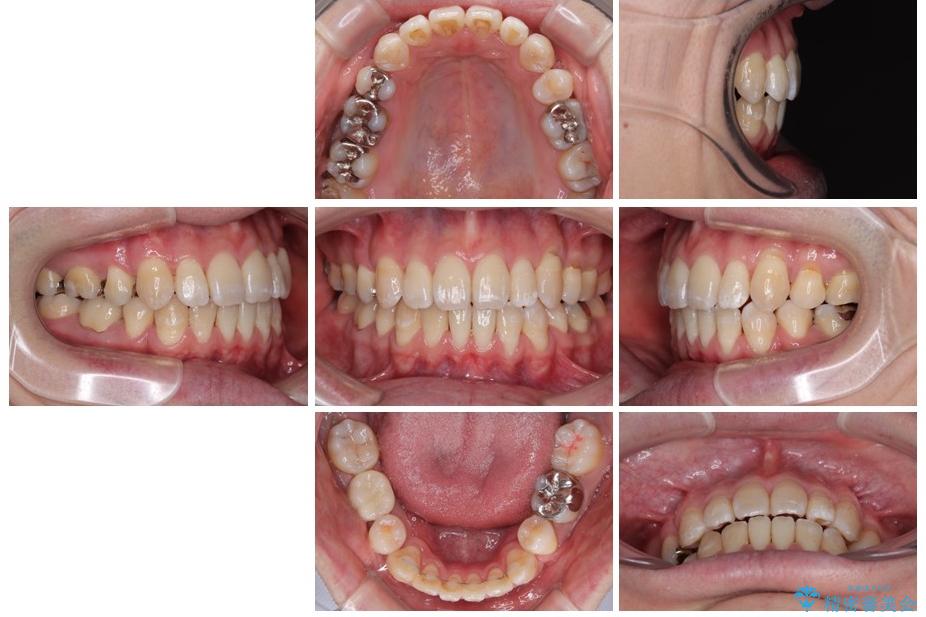

治療前

• 口元の突出感を改善!目立ちにくいワイヤー矯正で自信を持てる自然な横顔に 治療前画像

治療途中

• 口元の突出感を改善!目立ちにくいワイヤー矯正で自信を持てる自然な横顔に 治療途中画像

治療後

• 口元の突出感を改善!目立ちにくいワイヤー矯正で自信を持てる自然な横顔に 治療後画像